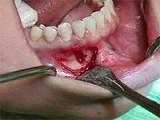

组图为牙瘤的外观及X 线表现,有关此病的描述错误的是 ( )

- A.绝大多数为恶性

- B.生长缓慢,早期无自觉症状

- C.由牙胚组织异常发育增生而形成

- D.X 线可见类似发育不全牙的影像

- E.多见青年人

正确答案及解析

A